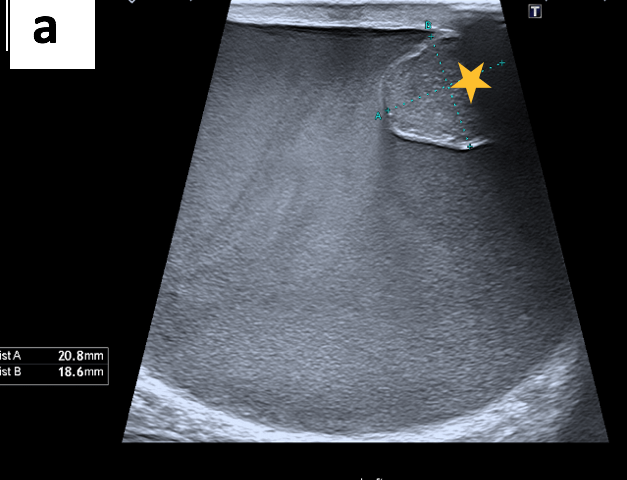

The ultrasound scan revealed turbid fluid with internal echoes and multiple hypoechoic, nodular, excrescences/adherent lesions on the tunica vaginalis. MRI scan was unremarkable.

Ultrasound is the primary imaging modality used to assess scrotal swelling or potential tumours. This is due to its easy availability, use of non-ionising radiation, cost-effectiveness and real-time features. However, ultrasound is highly operator-dependent and, therefore, requires adequate training. Other modalities, such as magnetic resonance imaging (MRI) or computed tomography (CT), can be considered when ultrasound findings are equivocal. Histology analysis of surgically removed (or biopsied) scrotal tumours is the gold standard for diagnosis. Although rare, tumours of the tunica vaginalis include fibrous pseudotumours and malignant mesotheliomas. They both primarily affect middle-aged men and are characterised by painless nodules and scrotal enlargement. The common sonographic appearance suggestive of MMTV includes the presence of singular or multiple painless nodules/excrescences in the tunica vaginalis with hydrocele. The diagnosis in this case was confirmed through orchiectomy followed by histopathology and immunochemistry.